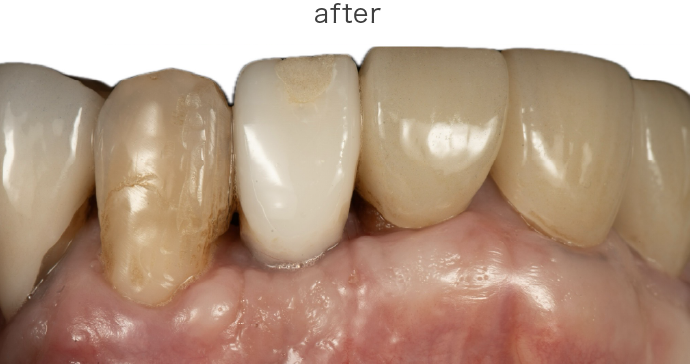

| 治療内容 | 上段 根面被服術(歯茎を上げる手術) |

| 治療費 | 総額 88000円〜 |

| 治療回数 | 1回 |

| リスク | 術部の発赤、腫脹、疼痛、部分的なネクローシス |

| 治療内容 | 全て 根面被服術(歯茎を上げる手術) |